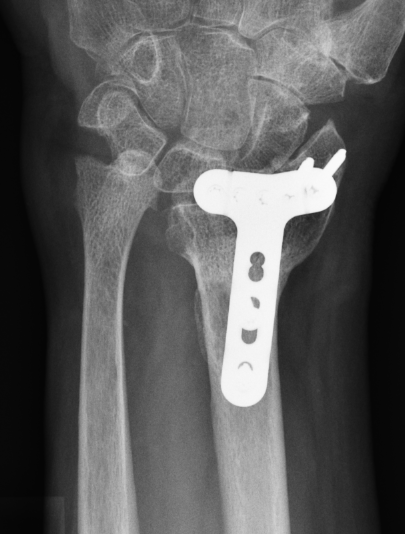

Complications of surgery

Nwosu et al J Hand Surg Am 2023

- systematic review of 1400 patients treated with volar locking plates

- 12% major complication

- median nerve injury 7%

- hardware removal 7%

- tenosynovitis 3%

- CRPS 2%

- malunion 1%

- infection 2%

- tendon rupture 1%

Tendon rupture

Azzi et al Plastic Reconst Surg 2017

- systematic review of tendon rupture after surgery

- 56 studies and 6000 patients

- volar plates: tendon rupture 1.5%, tenosynovitis 4.5%

- dorsal plates: tendon rupture 1.7%, tenosynovitis 7.5%

Flexor tendon rupture

Etiology

Plates distal to watershed mark

Prominent screws

Thicker plates

Incidence

Asadollahi et al J Orthop Traumatol 2013

- systematic review of flexor tendon rupture after plating of distal radius fractures

- 47 cases

- FPL 57%

- FDP to index finger 15%

Volar rim plates

Lari et al Eur J Orthop Surg Traumatol 2023

- systematic review of surgical treatment of volar rim fractures

- 26 studies and 600 patients

- implant removal 22%

- flexor tendon irritation 6%